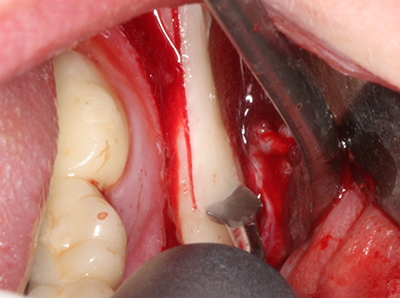

When surgical procedures are performed on bone in the immediate vicinity of sensitive structures such as blood vessels or nerves, rotary instruments pose a significant risk of iatrogenic injury. Piezoelectric devices can be helpful for preparation of bone covers and removal of hard tissue close to nerves, particularly for exposure of nerves after iatrogenic injury but also during nerve lateralization for resective and reconstructive procedures or implant placement (Fig. 17-20). Light contact between the piezotip and the nerve does not generally result in damage but proceeding incautiously with saw-like motions or attachments where a residual bone substrate remains may cause temporary or even permanent nerve damage. However, the risk of damage is considered to be substantially lower than when using saws or milling instruments (Pereira, Gealh et al. 2014).

Fig. 20: The removed bone cover is re-adapted and fixed with an osteosynthesis screw (KLS Martin, Tuttlingen).